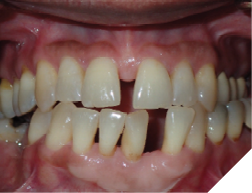

Fig. 2A

Fig. 2B

Fig. 2C

The majority of the orthodontic practices offer a period of “supervised retention” to their patients and communicates the customized retention recommendation with the patient’s general dentists. It is extremely important to work as a team to achieve long term clinical success in maintaining a functional bite and aesthetic smile. The general dentists continue to see their patients on a regular basis and have an opportunity to assess the orthodontic retainers and the bite after the supervised retention period is completed by the orthodontists. With great care, orthodontic retainers would serve for a long time (Fig. 1) without any major issues. However, in some cases, the failure to notice the clinical problems early on results in functional issues that would require a comprehensive orthodontic treatment to correct it (Fig. 2).